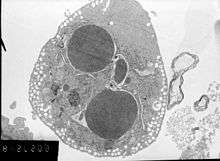

Methods for distinguishing apoptotic from necrotic (necroptotic) cells

In order to perform analysis of apoptotic versus necrotic (necroptotic) cells, one can do analysis of morphology by time-lapse microscopy, flow fluorocytometry, and transmission electron microscopy. There are also various biochemical techniques for analysis of cell surface markers (phosphatidylserine exposure versus cell permeability by flow fluorocytometry), cellular markers such as DNA fragmentation[53] (flow fluorocytometry), caspase activation, Bid cleavage, and cytochrome c release (Western blotting). It is important to know how primary and secondary necrotic cells can be distinguished by analysis of supernatant for caspases, HMGB1, and release of cytokeratin 18. However, no distinct surface or biochemical markers of necrotic cell death have been identified yet, and only negative markers are available. These include absence of apoptotic markers (caspase activation, cytochrome c release, and oligonucleosomal DNA fragmentation) and differential kinetics of cell death markers (phosphatidylserine exposure and cell membrane permeabilization). A selection of techniques that can be used to distinguish apoptosis from necroptotic cells could be found in these references.[54][55][56]